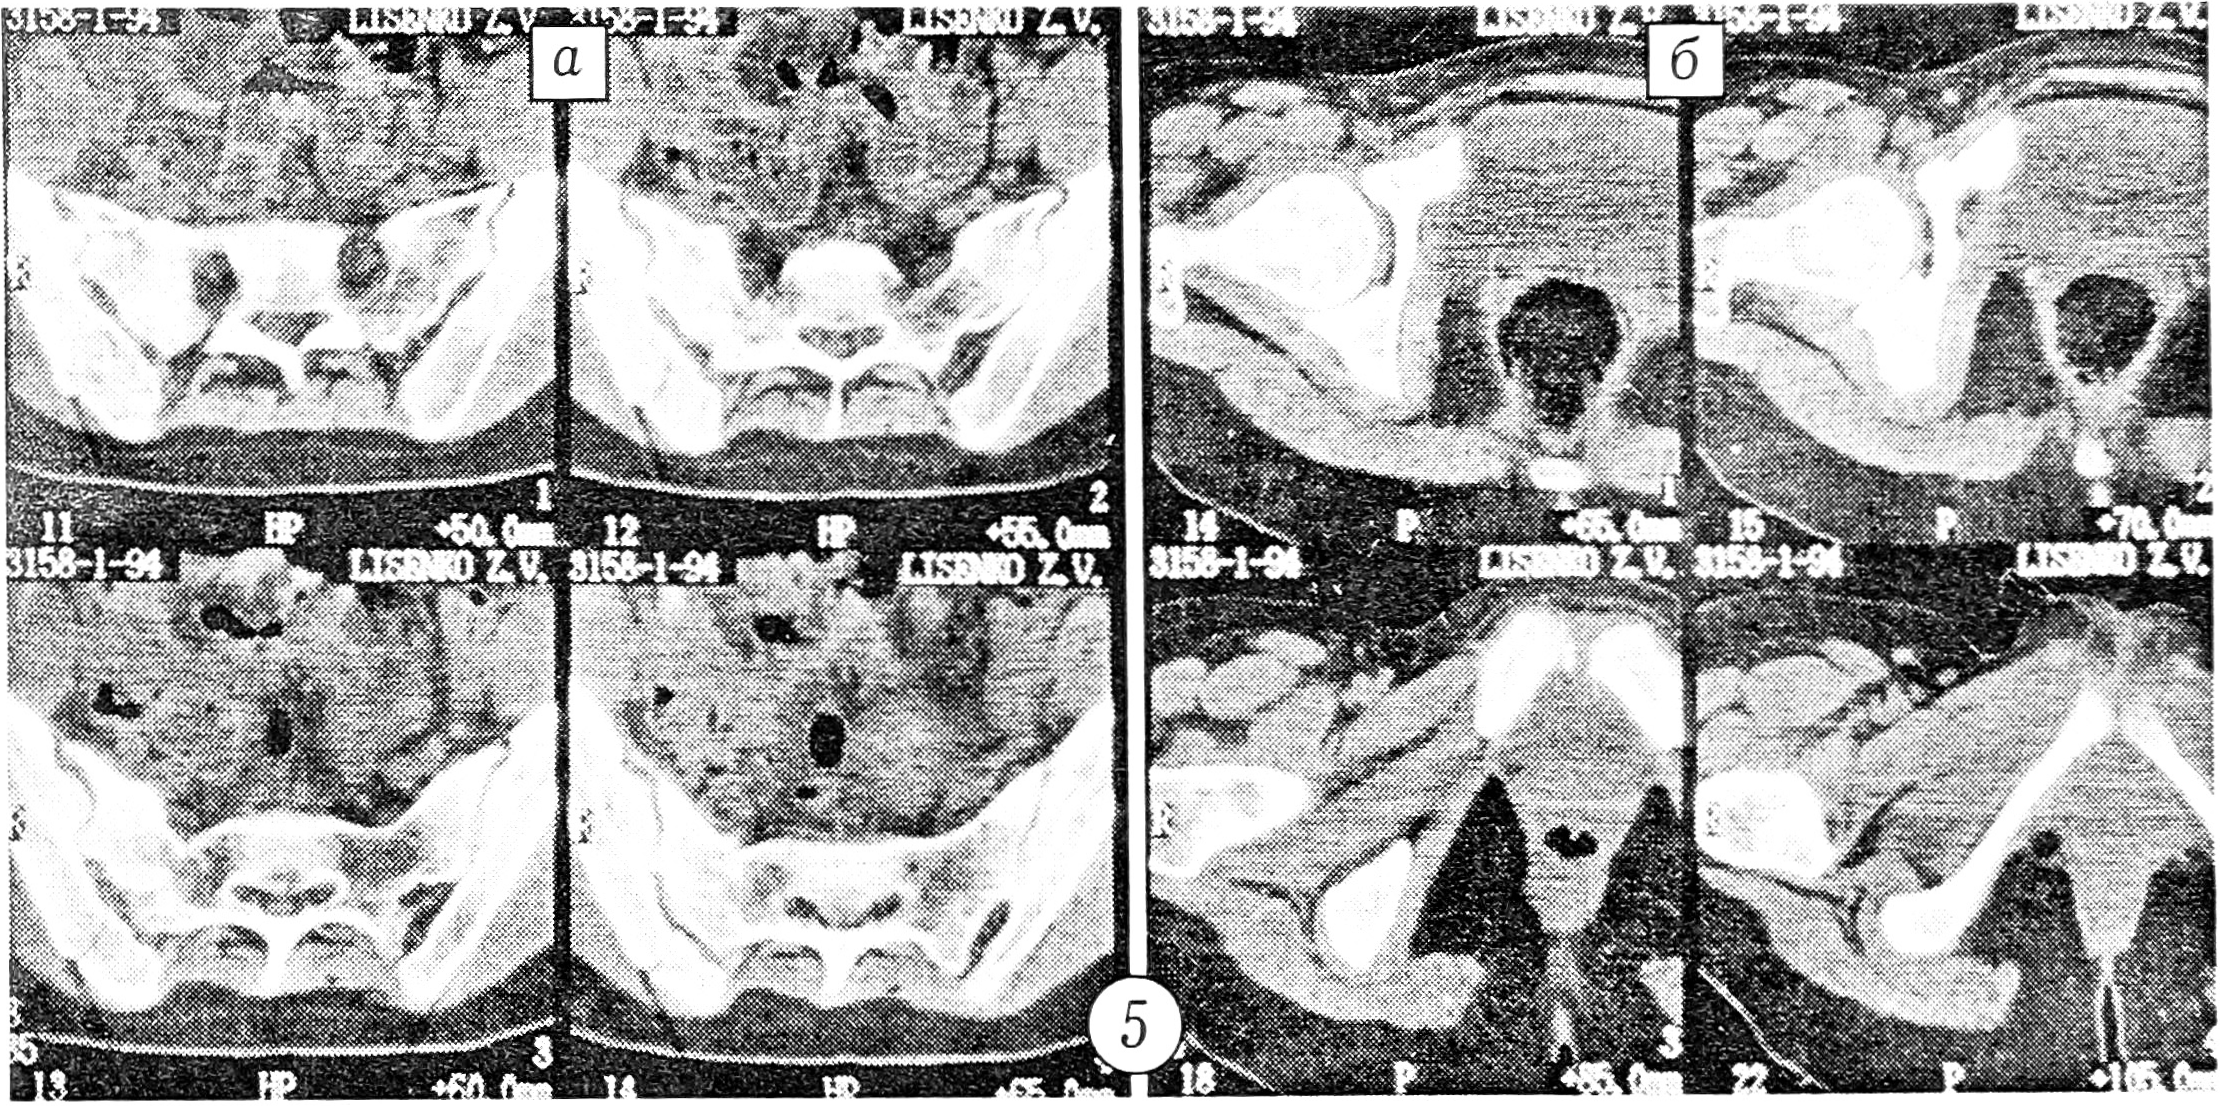

Больная Л., 23 лет, на рентгенограмме в стандартной переднезадней проекции выявлен перелом лонной и седалищной костей справа (рис. 4). При компьютерной томографии, помимо этого, обнаружены оскольчатый перелом боковой массы крестца справа (рис. 5, а) и отрыв костного фрагмента в области лонного сочленения (рис. 5, б).

Рис. 5. Компьютерные томограммы больной Л.

a — оскольчатый перелом боковой массы крестца и лонной кости справа; б — отрыв костного фрагмента в области лонного сочленения.